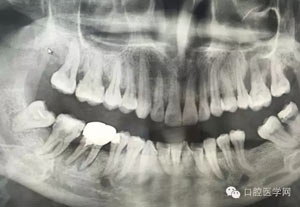

病例1:患者迫切希望保留自己的這一顆牙齒,根尖周陰影比較大,二度松動.而且旁邊有種植修復(fù)體,和患者溝通好后,治療好后觀察一個月后冠修復(fù),因為有種植的后期修復(fù),所以有了機會觀察,術(shù)后三個月和術(shù)后四個月,根尖恢復(fù)的還算不錯,希望能夠繼續(xù)觀察下去.這樣子的病例,做的時候我們一定要非常的小心,和患者要有充分的溝通以及不同科室的溝通然后決定怎么樣做比較好,假如就是出現(xiàn)了問題,到時候我們也比較好處理些,免得我們自己到時候不好收場。